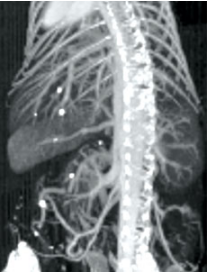

AuroVist 15 nm成像結(jié)果展示:

|

| 注射AuroVist 15 nm X射線造影劑后小鼠體內(nèi)顯微CT。 | 靜脈注射AuroVist-15nm后,活體小鼠腿部和骨盆區(qū)域周圍的20um血管顯微CT。 |